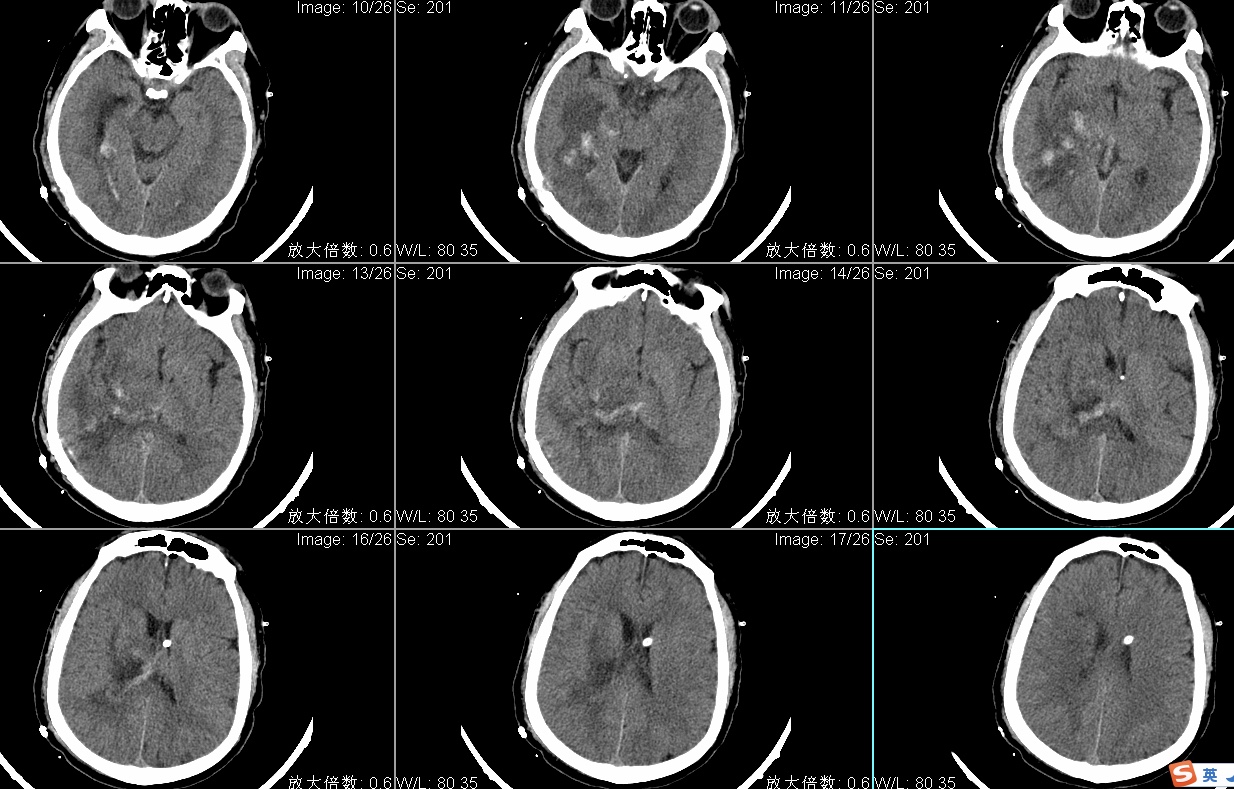

头CT显示右侧丘脑出血破入脑室多田公式计算出血量约50ml;

手术入路:神经内镜辅助右丘脑出血清除术。